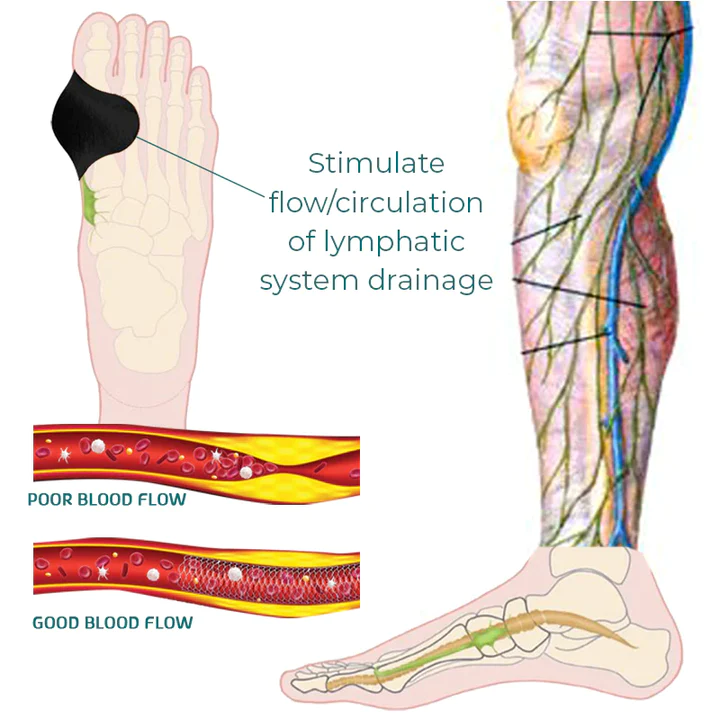

- This patch aids in stimulating the lymphatic system, which helps lymph fluids move throughout the body and improve circulation, as well as reducing pain and swelling, accelerating metabolism, and easing stiff joints.

- RASSMAM™ BunionOut Relief Patch are made to straighten your big toe and put it back in its proper place. It not only relieves your toe from the pain, swelling, and pressure brought on by bunions, but it also aids in reducing the bunion so that the joint won’t become misaligned once again. Relieve pain and overlapping toes without surgery.